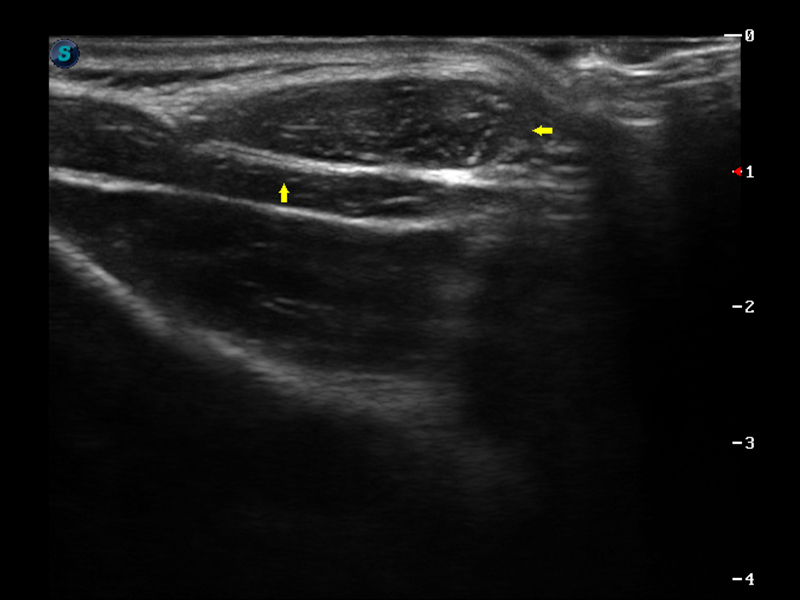

μ-Scan微米成像

脉冲反相谐波成像